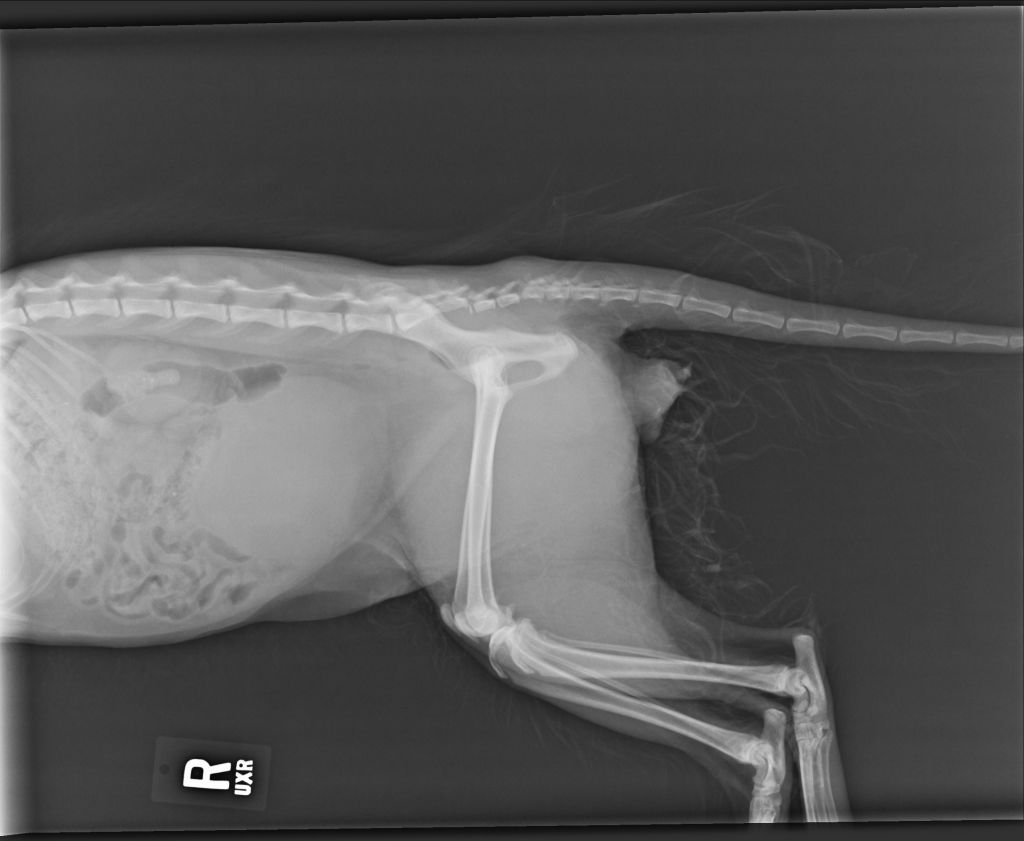

The cat’s spine was fractured in two places and couldn’t lift his tail or urinate on his own. He may have been kicked from behind or kicked while being dangled by his tail, the SPCA says.